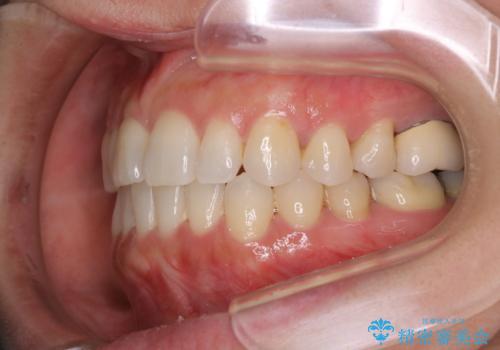

- 前歯のがたつきと反対咬合を主訴に来院されました。

インビザライン・クリンチェック(歯のシミュレーション)を行い、

インビザラインライトで治せる範囲であることを確認し治療を開始することになりました。

今回はクリンチェックを作成したのちに、枚数が少なくても可能であることが判明したためインビザラインライトでの治療を行いました。

最初はインビザラインモデレートパッケージの予定で契約をされていたので、金額も10万円以上安くなり仕上がりも満足頂きました。